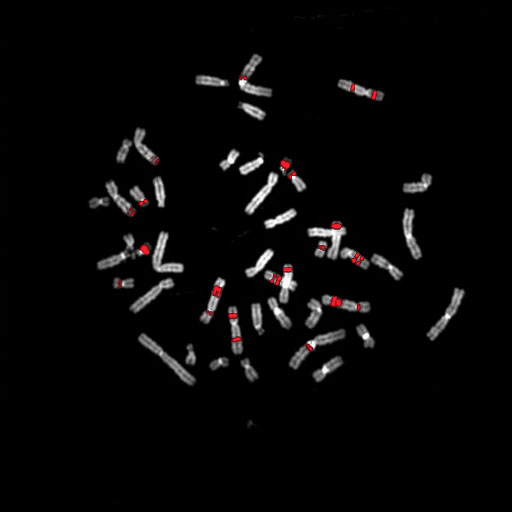

081 D